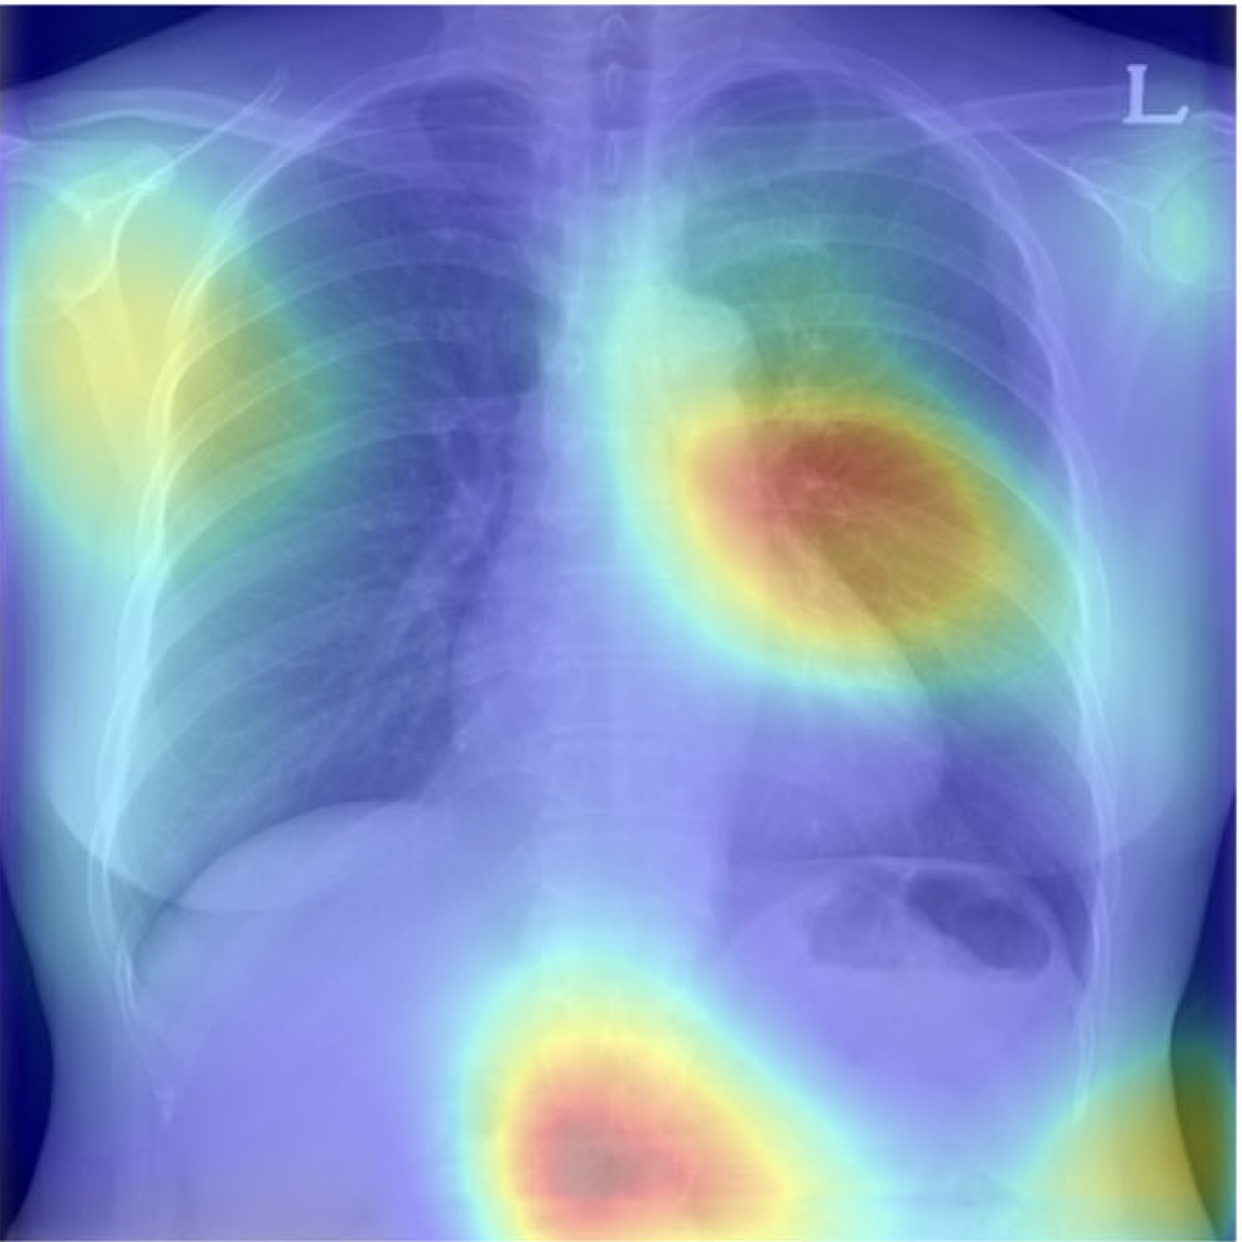

First-In-Class, CXR-based Osteoporosis screening

1. Since Osteoporosis is an asymptomatic disease, CXR-based disease screening methods can be used as effective early detection tools for these high-morbidity diseases.

2. Promedius’s deep-learning-based OsPor-screen model found a correlation between DEXA scan images and simple CXR scan images that can ensure financial incentives for disease screening than costly conventional methods through external validation.

3. Considering the global trend of AI adoption in healthcare, we believe our robust OsPor-screen model can be covered by reimbursement entities to help early detection of osteoporosis and patient monitoring.